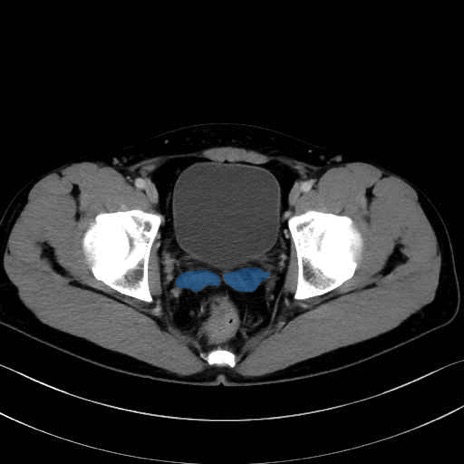

精嚢(seminal vesicle)のCT画像における解剖

症例

【症例】20歳代 男性 スクリーニング